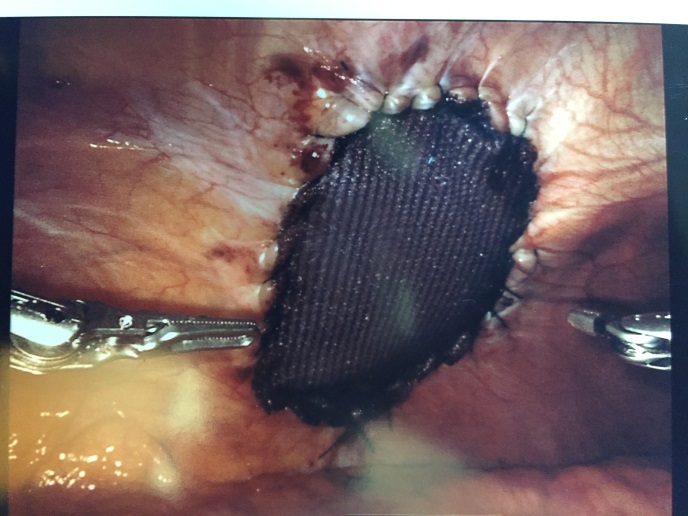

The intercostal defect was measured and a 7.6 x 13 cm. oval shaped Sepramesh (Bard Davol Inc. Providence RI) was brought onto the surgical field. Primary closure of the defect was not performed. The mesh was anchored in place at the antero-medial and posterolateral ends utilizing 2-0 Vicryl (Ethicon Inc, Somerville, NJ). The mesh was then affixed circumferentially utilizing a 2-0 V-lock (Medtronic, Fridley, MN) suture in a running fashion with a 2cm. overlap of normal tissue. The ribs were not incorporated in the suture (Figure 4).

Patient #2: An open Hasson technique in the left upper quadrant was employed to gain intra-abdominal access. Three additional 8 mm working ports were placed, one in the left mid-abdomen, and one in each lower quadrant respectively. The patient was placed in reverse Trendelenburg and rotated to the left. The hernia contents were easily reduced into the peritoneal cavity. Primary closure was not performed. A 15 x 20 cm. Sepramesh was used to cover the defect and circumferentially sutured in place utilizing 2-0 V-Loc suture. The ribs or periosteum were not intentionally incorporated in the suture or mesh. Satisfactory coverage of the defect with approximately 2 cm. overlap of normal tissue was noted at the end of the case. The robot was undocked, pneumoperitoneum (abnormal presence of air or other gas) evacuated, ports removed, and the dominant 12 mm port site fascia closed utilizing O Vicryl suture.